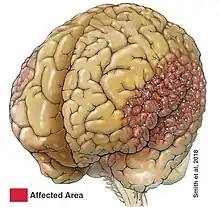

| Bilateral perisylvian polymicrogyria | |

Bilateral perisylvian polymicrogyria (BPP)

BPP is similar to the other types of polymicrogyria in that it is usually symmetrical, but BPP can vary among patients. BPP is characterized by its location; the cerebral cortex deep in the sylvian fissures is thickened and abnormally infolded, as well as the sylvian fissures extending more posteriorly up to the parietal lobes and more vertically oriented.[2] BPP has been classified into a grading system consisting of four different grades that describe the variations in severity: